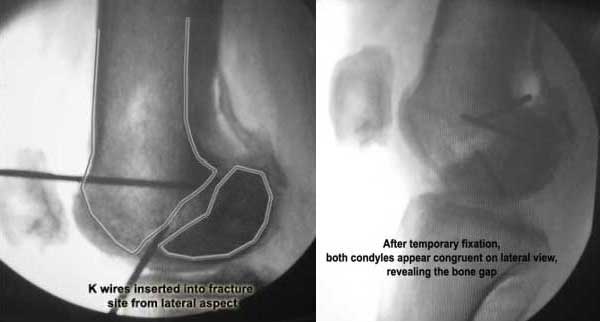

Applied a distractor between femoral shaft and tibia, to create a space on the lateral aspect.

This brought the lateral condylar fragment into a position that seemed to be reasonably well aligned, but showed up a bone gap.

This was fixed temporarily, bone grafted with tricortical struts, and fixed by two cancellous screws. The fragment was not large enough to afford any fixation to a plate or such implant, and the screws held it compressed well to the rest of the distal femur.